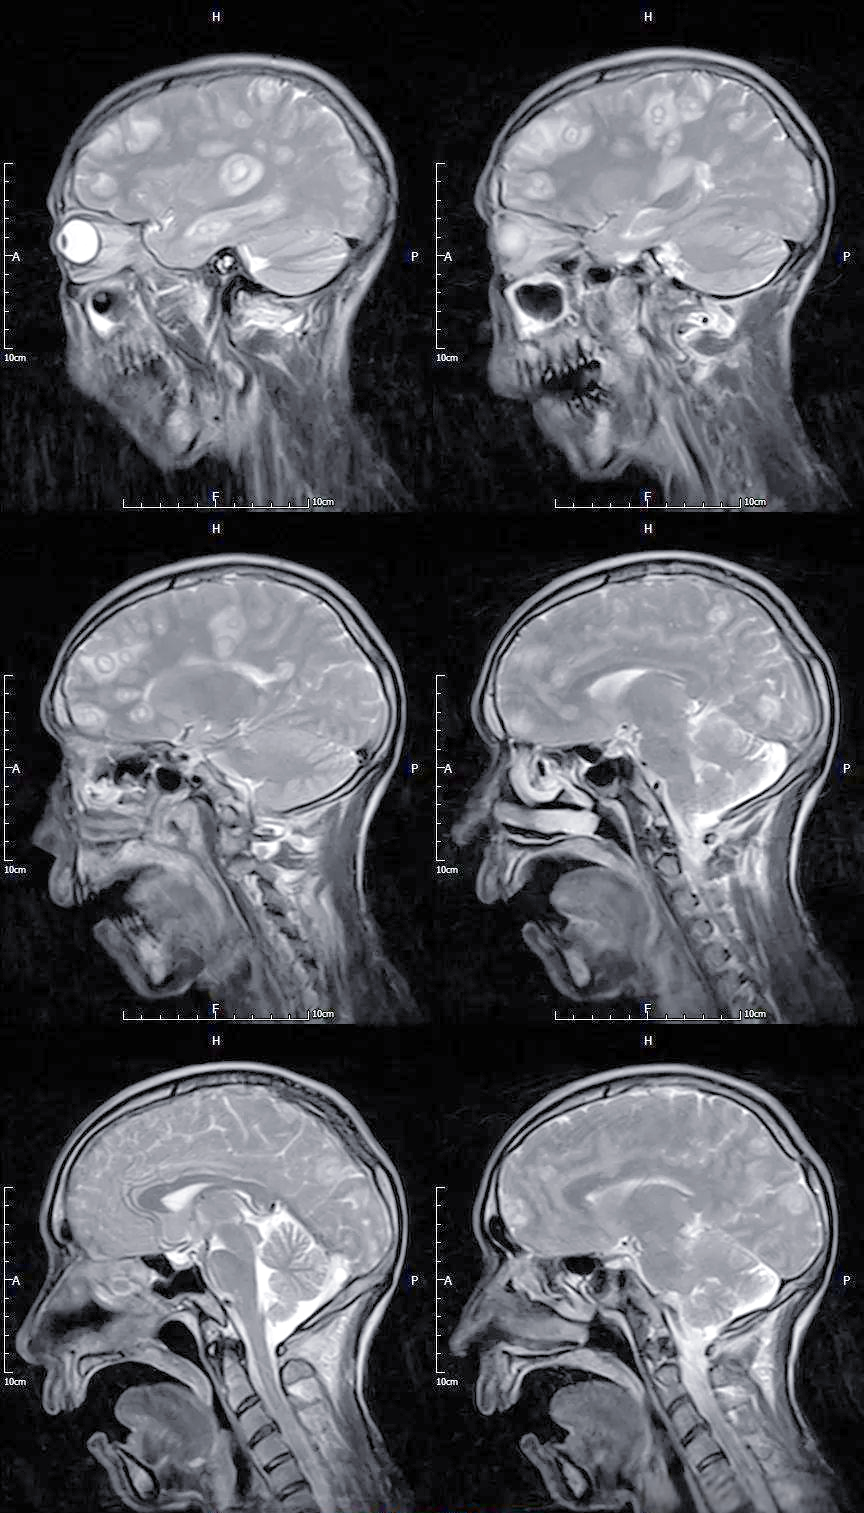

脑囊虫病

术语缩写脑囊虫病(neurocysticercosis,ncc)同义词囊虫病定义由猪肉

囊虫病:一种常见的中枢神经系统寄生虫感染